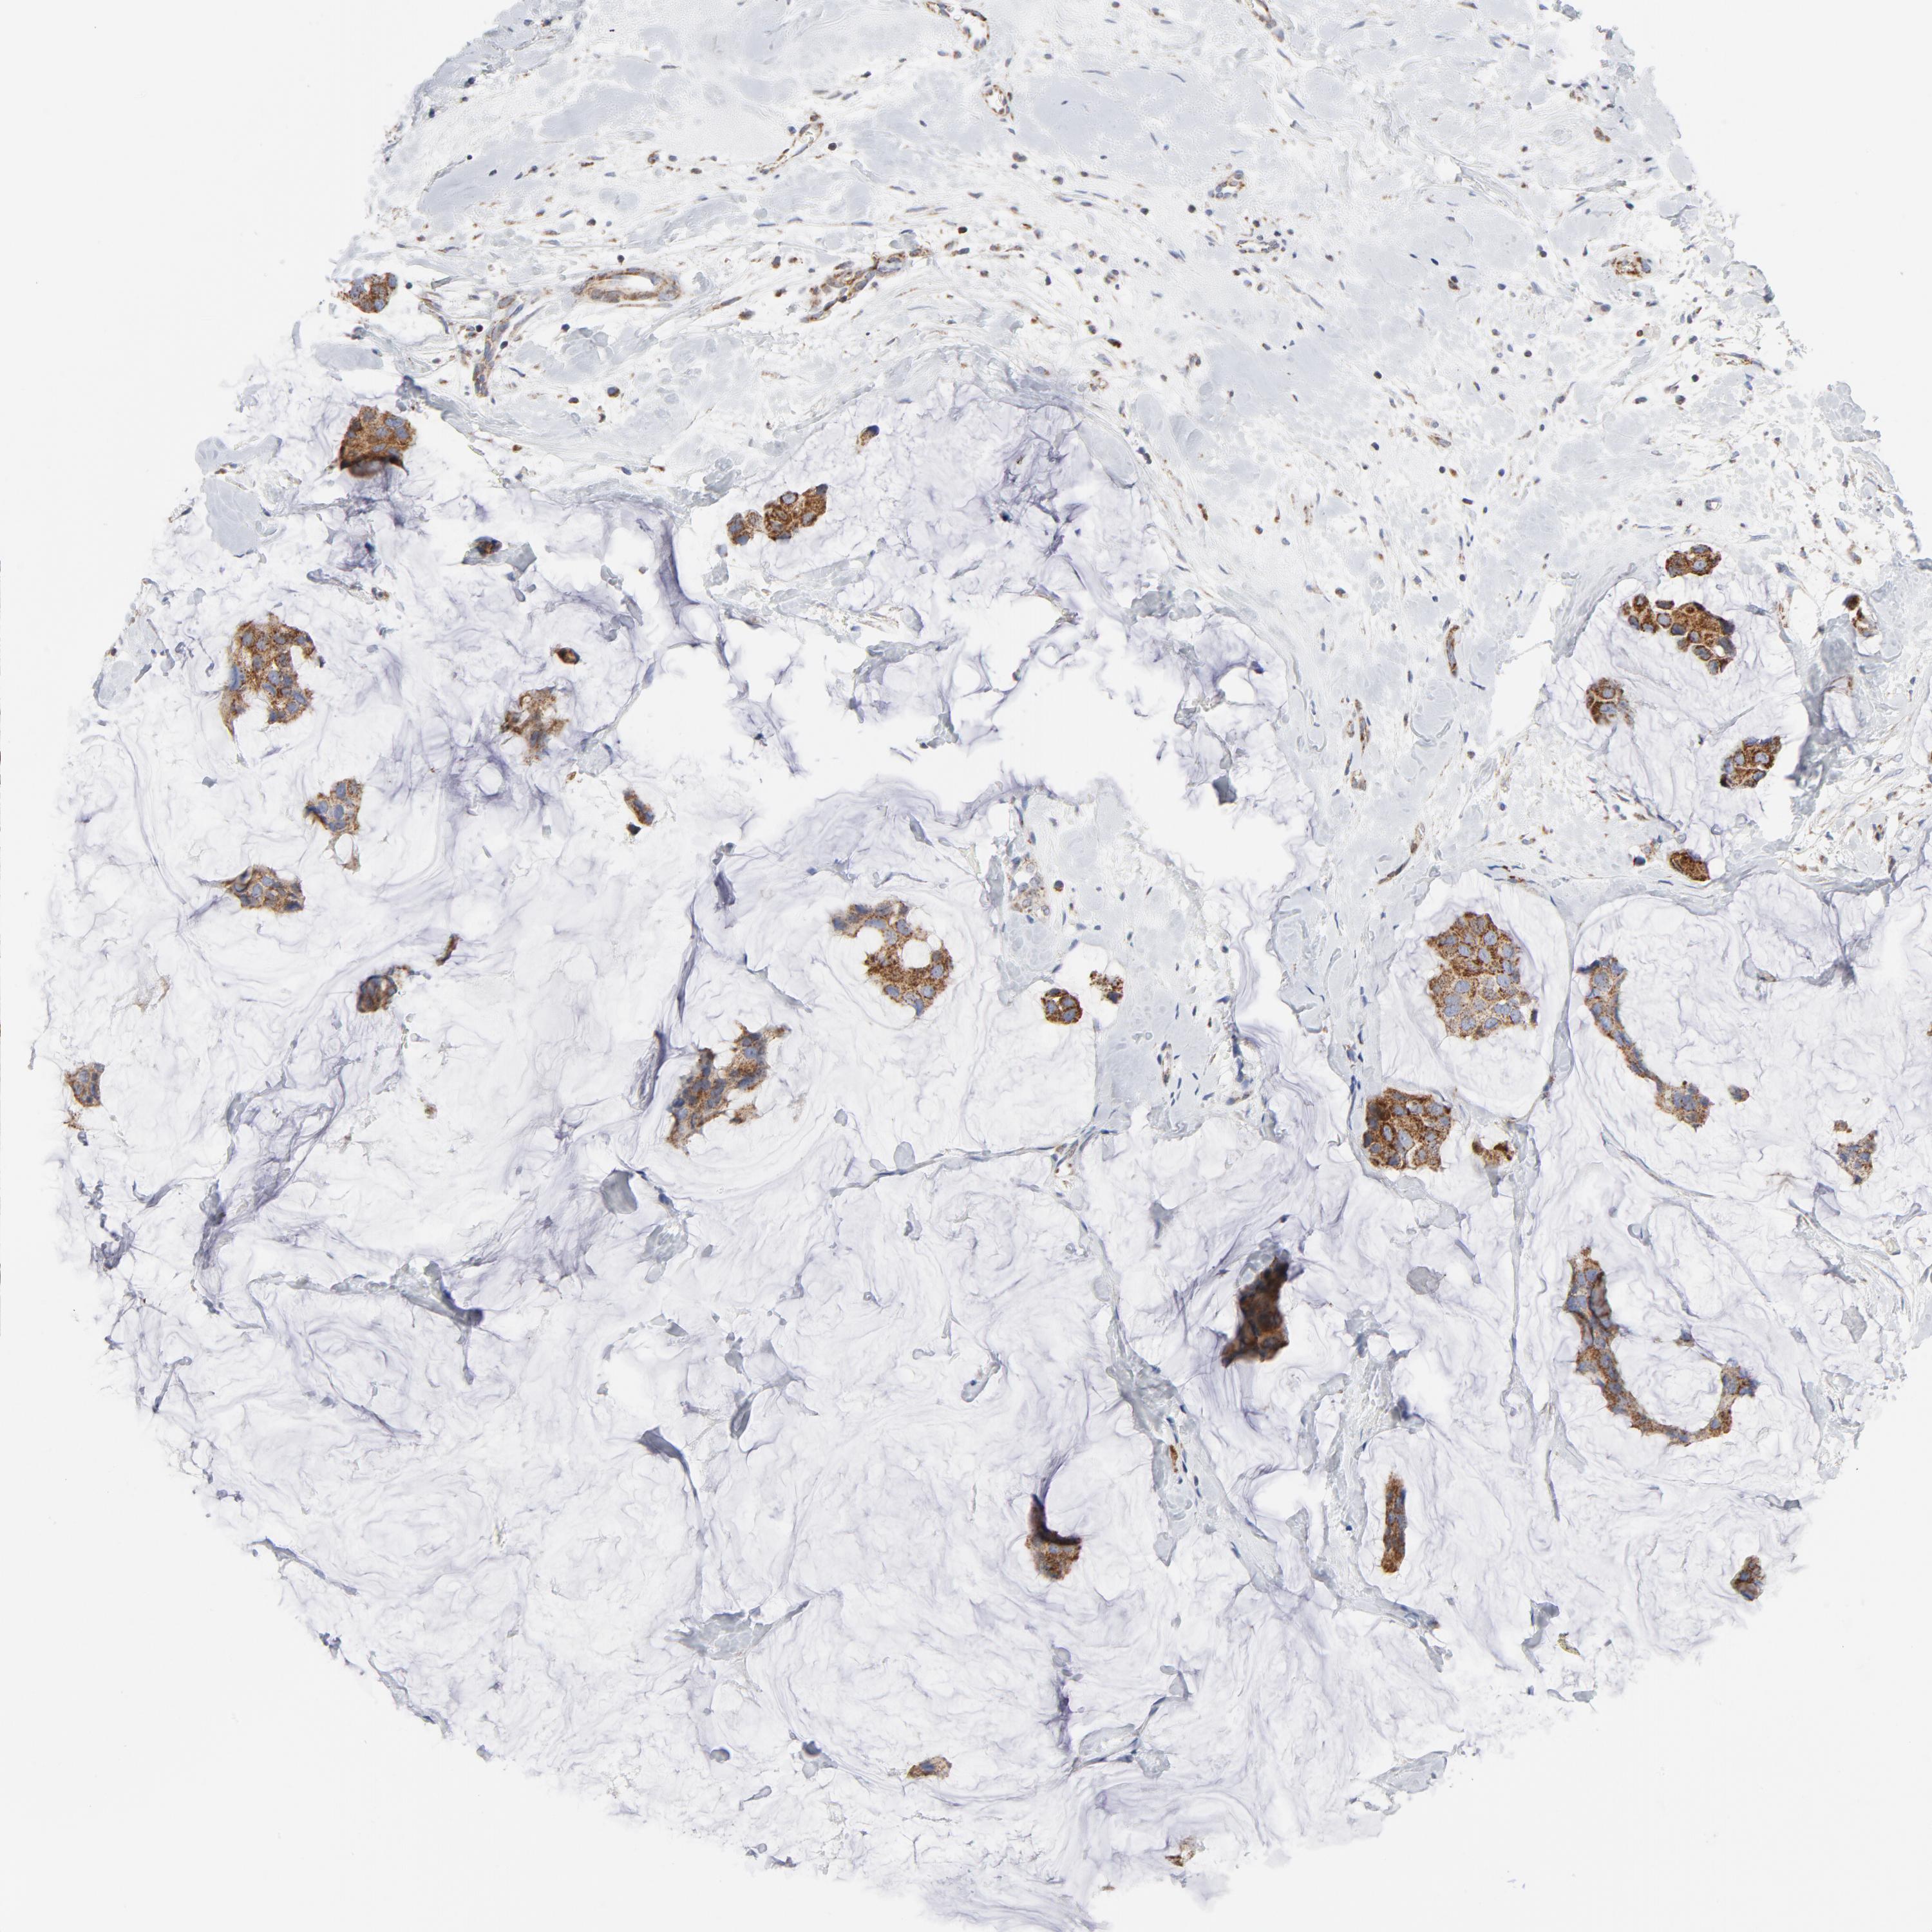

CANCER BREAST CANCER Show tissue menu

BRCA TCGA BRCA VALIDATION PROTEIN EXPRESSION

ANTIBODIES

AND

VALIDATION